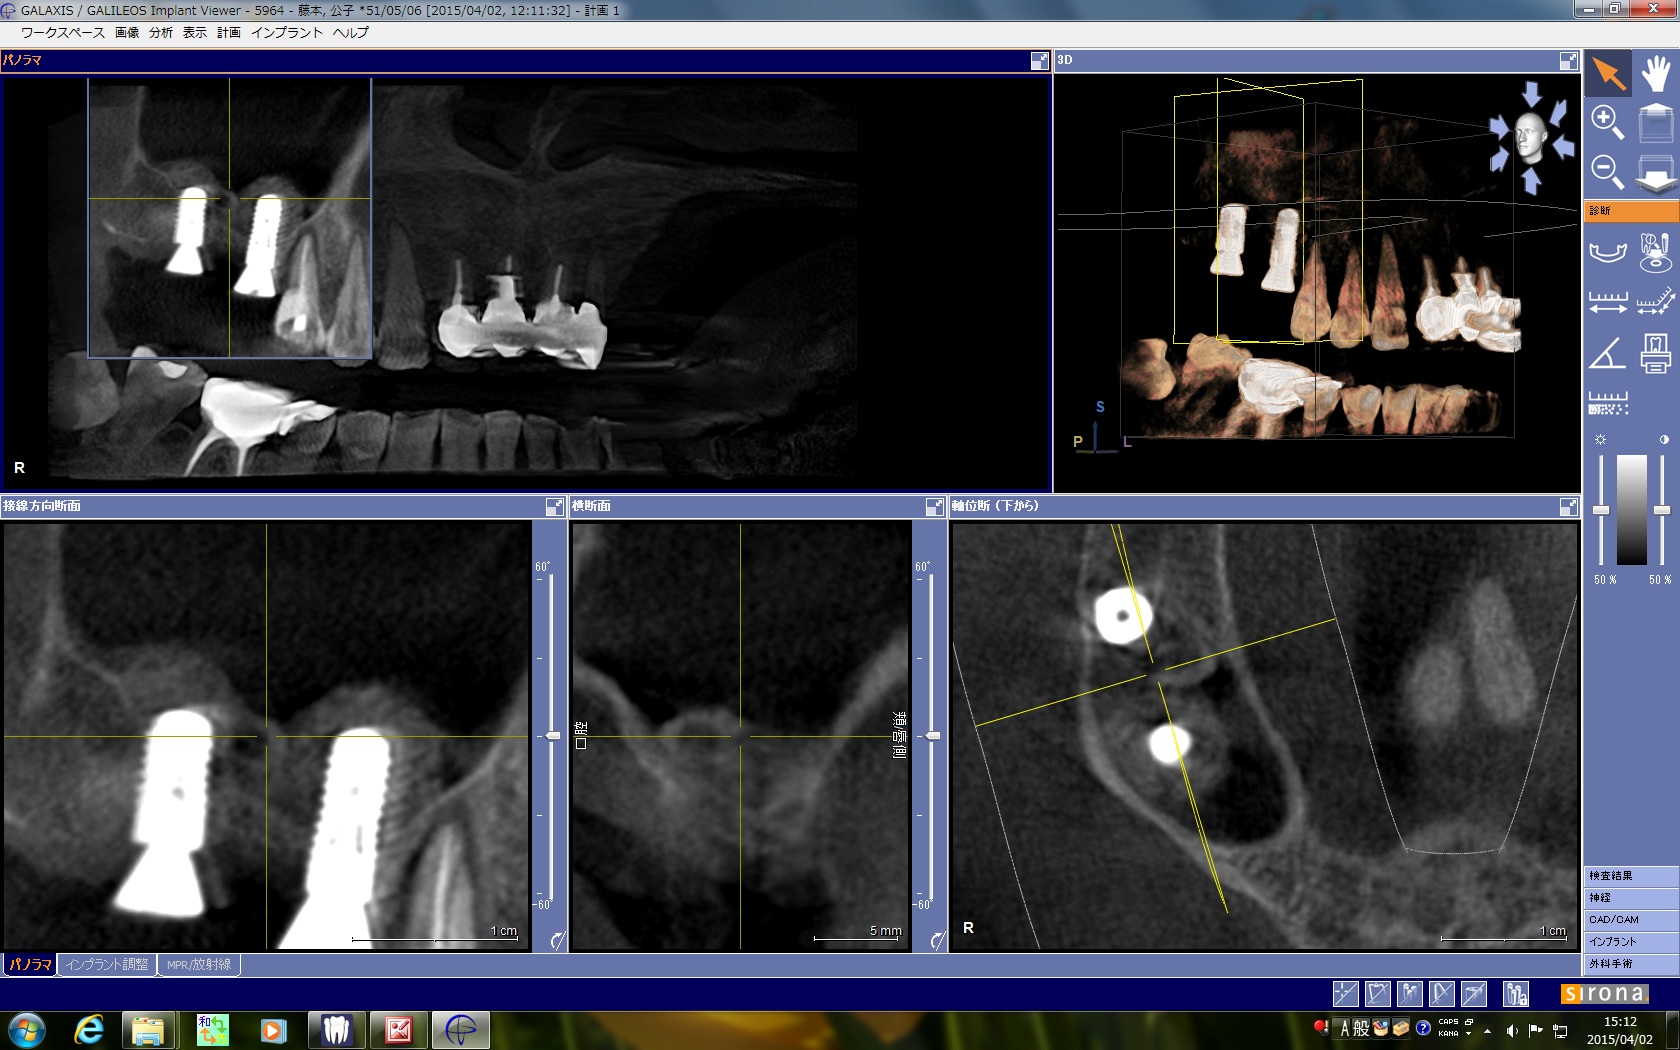

術前のCTで上顎洞の中に骨瘤起が見られました。

術前のCTでは、上顎洞内にまん丸い不透過像が見られます。たぶん骨と思われます。

術後の所見ですが、ポジショニングもまずまずですね。

術後のCTですが、うまく補填材がドーム状に入っているのがわかります。